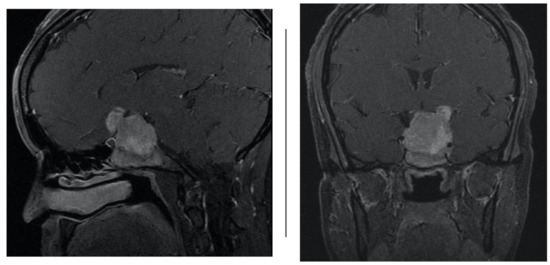

Each patient subsequently presented at various time points after surgery with a low-grade CSF leak from the nares on a clinical exam that was found when the patient bent forward, confirmed by both a board-certified neurosurgeon and otolaryngologist. Cerebrospinal fluid was sent for B2-transferrin, which was confirmatory in all cases. Each patient then underwent a CT scan of the brain to rule out pneumocephalus (Figure 1) and hydrocephalus, and then subsequently underwent a high-volume lumbar puncture, where 30–40 cc of CSF was removed from the intrathecal space and sent for analysis, including Gram stain and culture. The patient was then started on acetazolamide 250 mg three times a day for 10 days and observed for two nights in the hospital [12].

Inclusion criteria comprised the following: (1) patients older than 18 years old; (2) patients with less than 1 cm3 of pneumocephalus on CT brain non-contrast (Figure 1); and (3) patients with only mild CSF leaks from the nose that could only be elicited when the patient bent forward. Patients were excluded from our analysis if they presented with signs/symptoms of meningitis as evidenced by clinical (high fever, meningismus, and nausea/vomiting) and laboratory analyses (blood cultures, and CSF profile/staining), or if they had high flow CSF leaks that would not be amenable to this conservative approach. Of note, the senior surgeon maintains a prospective log of all transsphenoidal surgeries done at our center; we included all patients who met the above criteria, regardless of whether they failed this conservative management or not.

Figure 1. CT brain non-contrast performed after presentation for suspected CSF leak confirming no pneumocephalus.